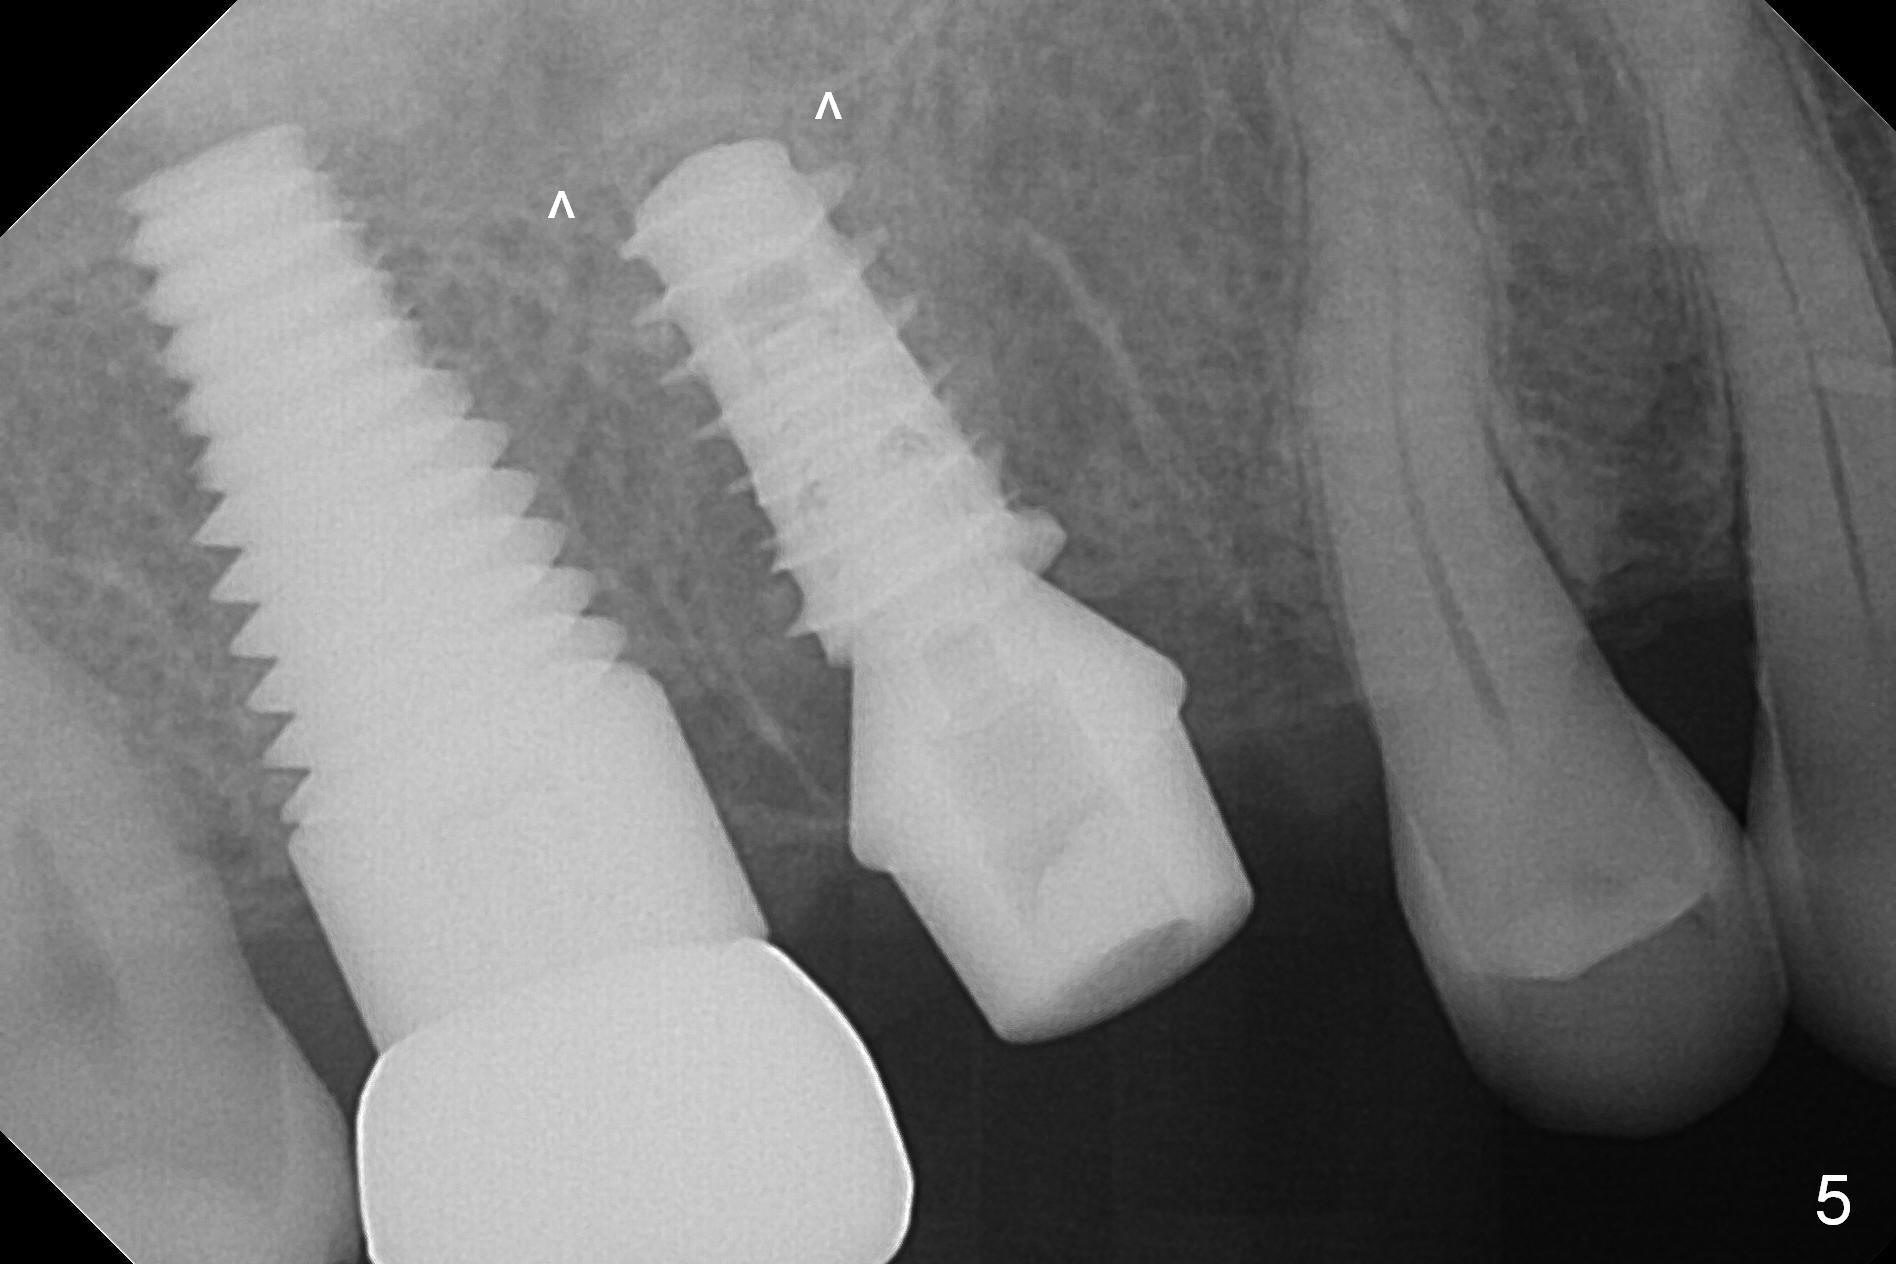

Heavy bruxism is characterized by the crack at #3 (symptomatic, requiring emergency extraction) and loss of the palatal cusp at #5 (Fig.1). Osteotomy is initiated in the septal slope (Fig.2 S) with a 1.6 mm pilot drill for 9 mm (with sudden empty feeling), followed by Marking bur. After 4.3 mm Magic Drill is used for ~ 9 mm, the sinus membrane is found to perforate. A dummy implant (5x9 mm, 2 mm shorter than design) is placed short of the sinus floor (Fig.3 ^). Prior to placement of 5.5x9 mm IBS implant (~ 35 Ncm, Fig.4,5), a piece of Osteogen plug is inserted into the osteotomy for repair of the perforation. The final implant is also shy of the sinus floor (Fig.5 ^). The Osteogen plug is apparently placed underneath the sinus floor so that it should be able to repair hard and soft tissue defects. The remaining sockets are mainly filled with Osteogen plug, while the implant plateau is covered by autogenous bone and Osteogen. When a 6.5x4(3) mm abutment is placed, an immediate provisional is fabricated (Fig.6) with its margin placed subgingival (Fig.6 inset dashed line). This innovative design of the provisional is to prevent collapse of the most coronal gingiva and loss of bone graft, particularly where the bony plate is defective. Although there is mild pain postop, nasal hemorrhage or discharge is absent.